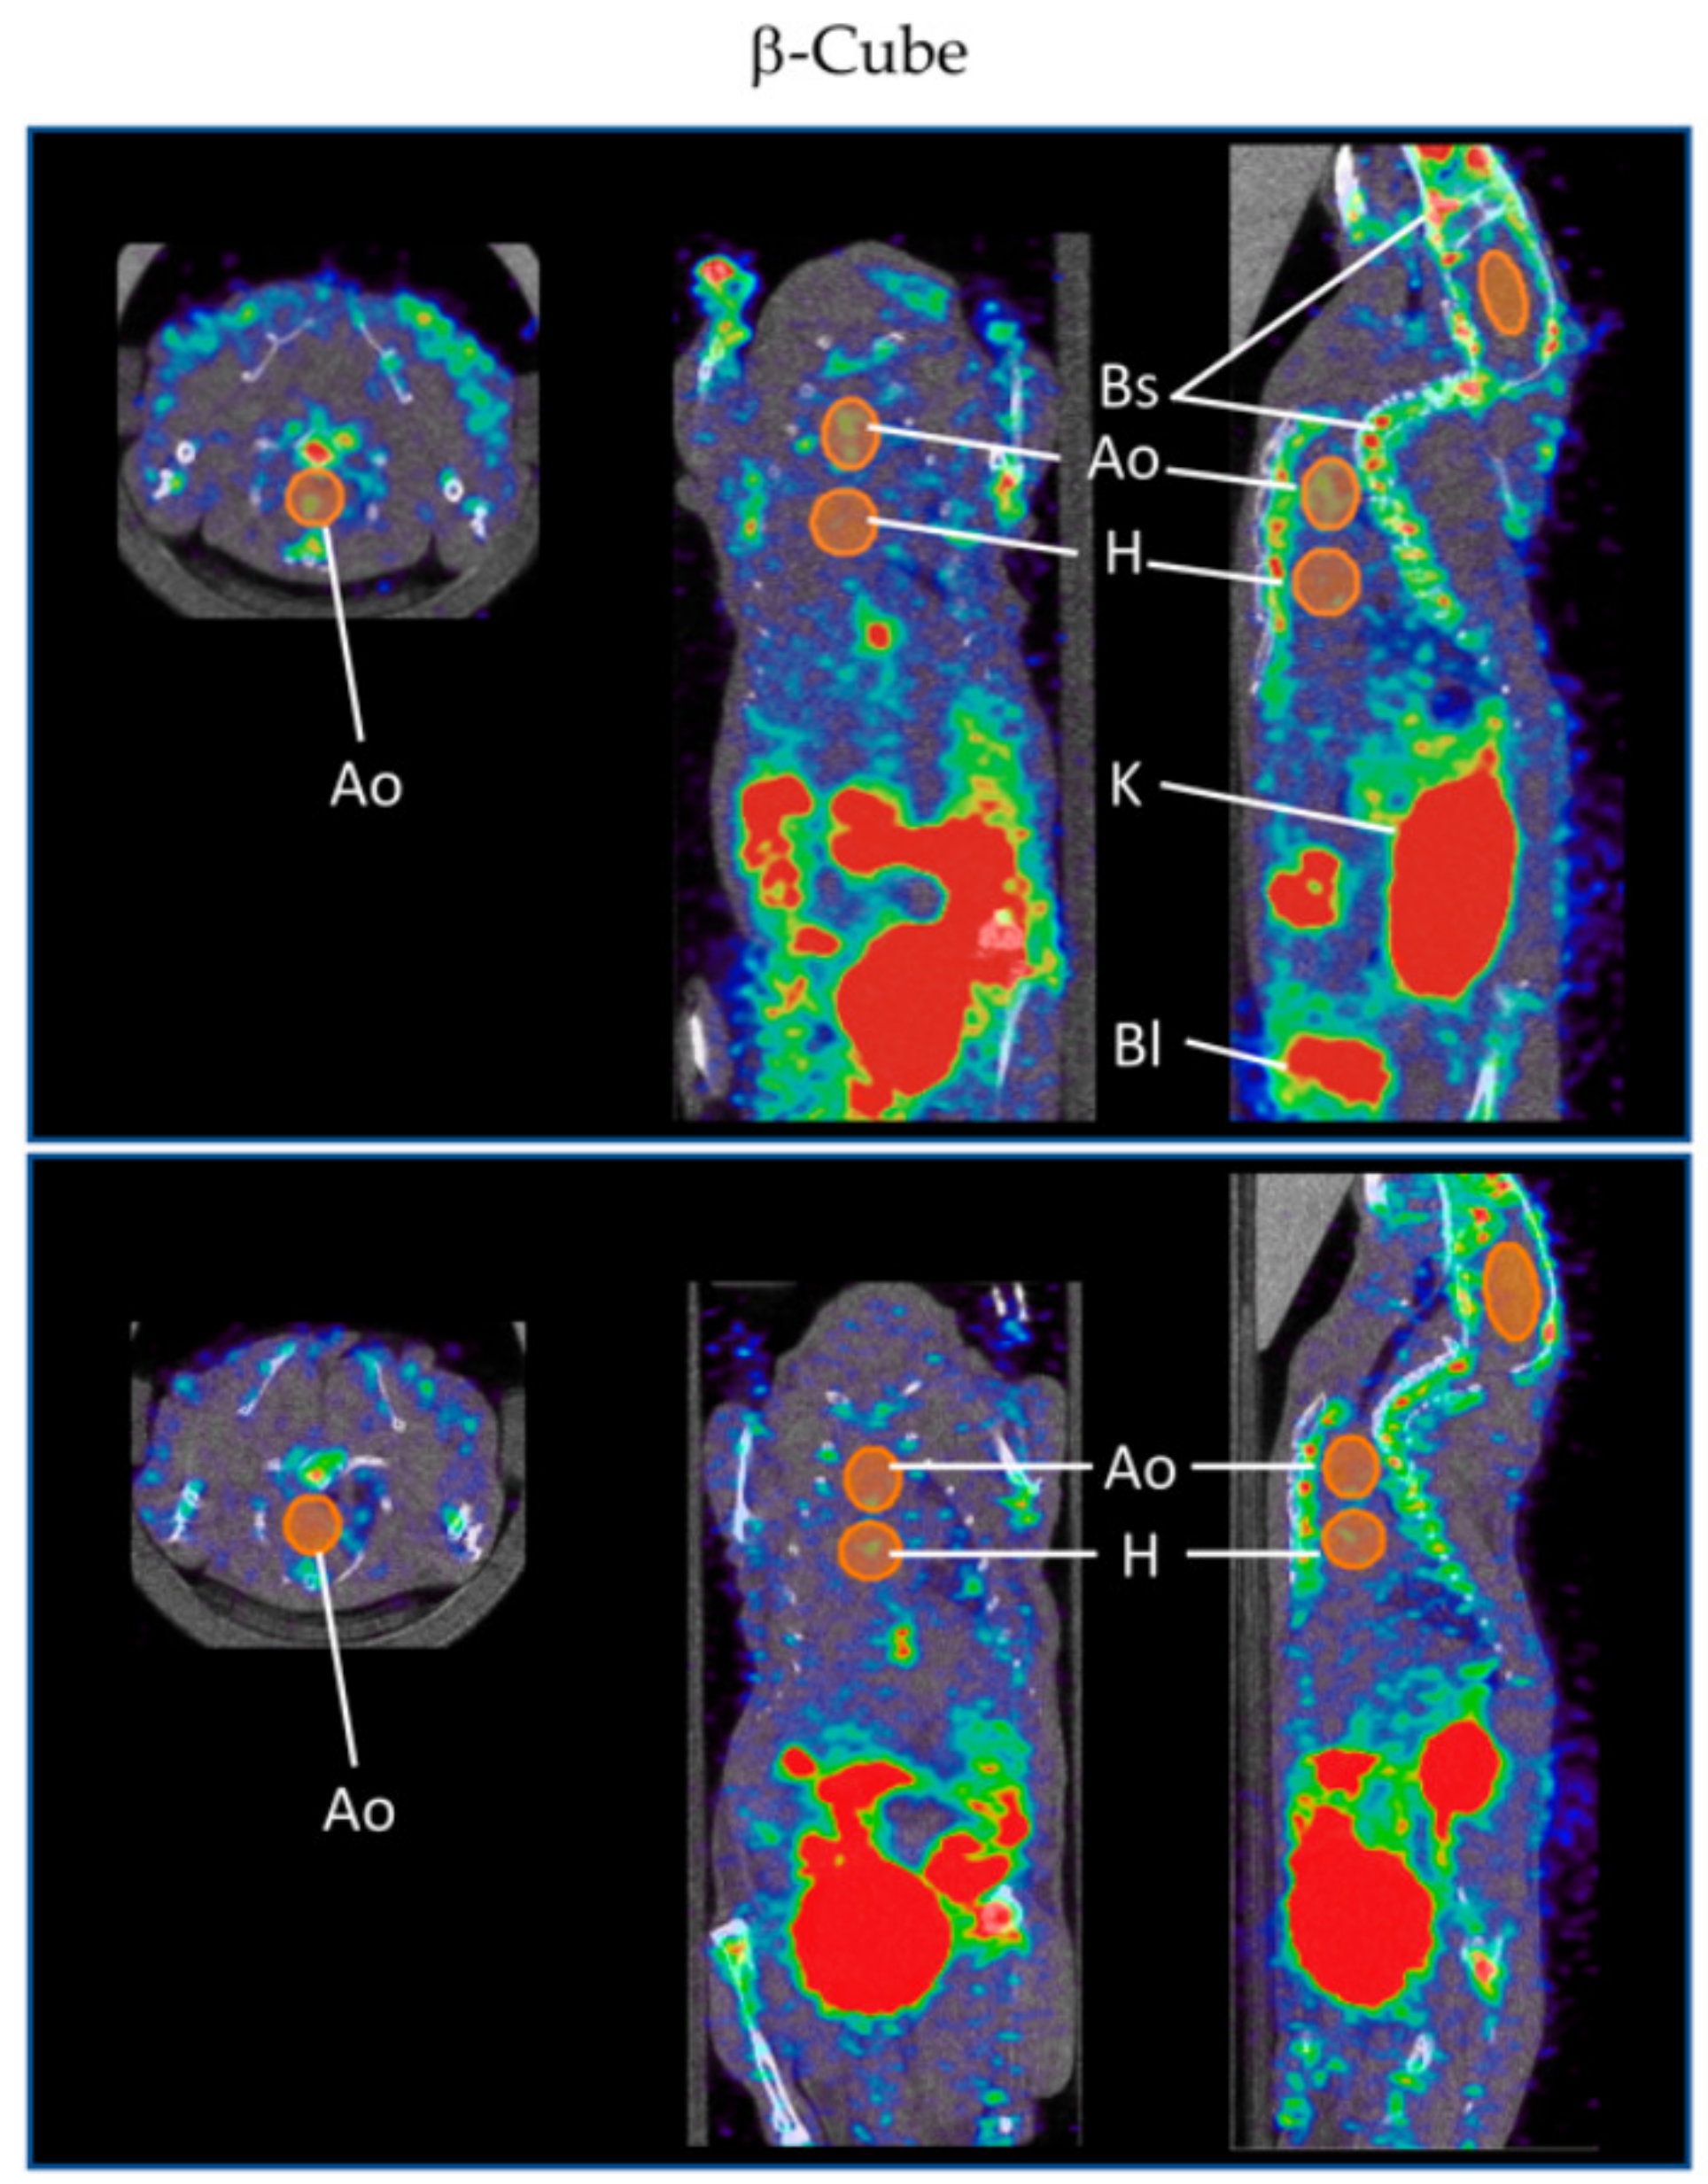

- Bridoux, J.; Neyt, S.; Debie, P.; Descamps, B.; Devoogdt, N.; Cleeren, F.; Bormans, G.; Broisat, A.; Caveliers, V.; Xavier, C.; et al. Improved Detection of Molecular Markers of Atherosclerotic Plaques Using Sub-Millimeter PET Imaging. Molecules 2020, 25, 1838. [Google Scholar] [CrossRef]

| Nuclear imaging | Fluorine-18 | Nanobody (cAbVCAM-1-5) | In vivo and ex vivo: ApoE−/− on WD | [115] |